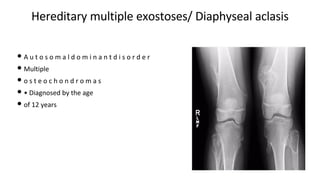

Hereditary multiple exostoses/ Diaphyseal aclasis

• A u t o s o m a l d o m i n a n t d i s o r d e r

• Multiple

• o s t e o c h o n d r o m a s

• • Diagnosed by the age

• of 12 years